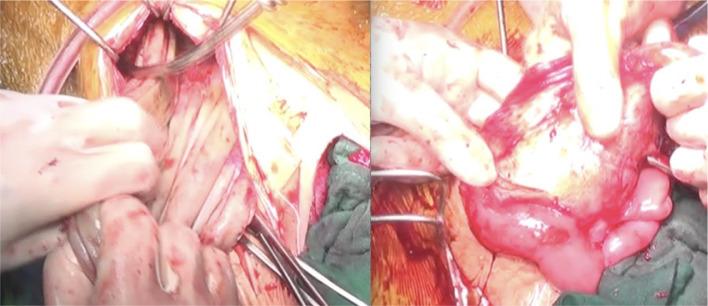

Desmoid tumors, also known as deep fibromatosis or desmoid-type fibromatosis, represent a rare subset of deep fibromatoses. It is a locally aggressive tumor, with no specific symptoms, and no metastatic potential. We report a case of a 38-year-old male patient with an abdominal mass. Radiological findings showed 2 tumors, the first was a solid inguinal mass of the left lateral iliac pedicle, and the second was a giant cystic mass in the abdominal cavity. An elective explorative laparotomy was performed to remove the 2 masses. Histopathological examination confirmed the desmoid tumor diagnosis of both lesions.

硬纤维瘤,也称为深部纤维瘤病或硬纤维瘤型纤维瘤病,是深部纤维瘤病中罕见的一种类型。它是一种局部侵袭性肿瘤,无特异性症状,也无转移潜能。我们报告一例38岁男性腹部肿块患者。影像学检查发现两个肿瘤,第一个是左侧髂蒂的实性腹股沟肿块,第二个是腹腔内的巨大囊性肿块。进行了择期剖腹探查术以切除这两个肿块。组织病理学检查证实两个病变均为硬纤维瘤。